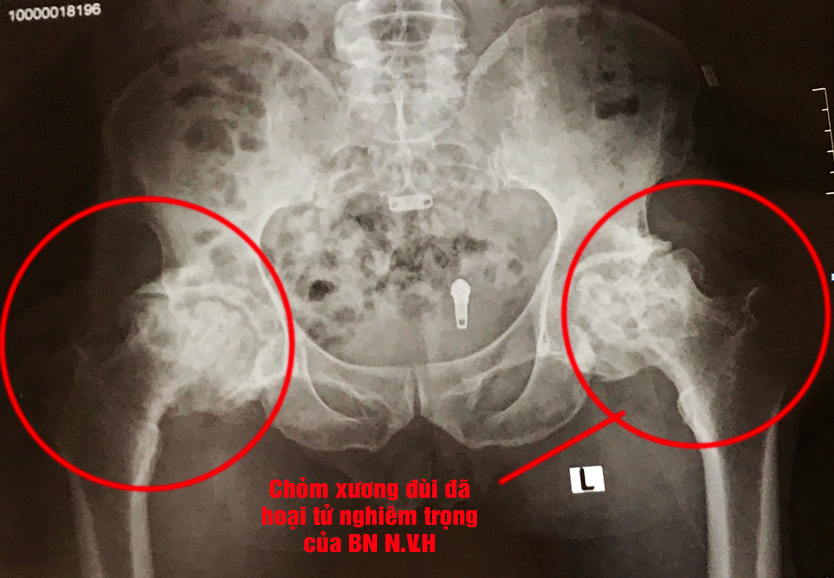

Điều trị bệnh nhân hoại tử chỏm xương đùi nghiêm trọng tại TTYT huyện Tam Nông

Người bệnh N.V.H (75t, Thanh Uyên) nhập viện tại Khoa YHCT & PHCN - TTYT huyện Tam Nông trong tình trạng: Đau nhiều khớp háng 2 bên, đau lan xuống mông và đùi, di chuyển đau nhiều và xuất hiện tiếng lục khục trong khớp, đi lại cần người hỗ trợ.

Theo BS CKI Nguyễn Quang Đạo – Trưởng khoa YHCT & PHCN: "Hoại tử chỏm xương đùi là tình trạng chỏm xương đùi bị phá hủy do thiếu nuôi dưỡng. Bệnh thường xảy ra ở độ tuổi thanh niên hoặc trung niên (30 – 60 tuổi).

Hoại tử chỏm xương đùi là nguyên nhân gây đau mạn tính và hạn chế vận động khớp háng. Người bệnh nằm trong những đối tượng có yếu tố nguy cơ cao như: tiền sử lao xương, tuổi cao, có tiền sử chấn thương, mắc bệnh lý chuyển hóa như: Đái tháo đường, rối loạn lipid máu… lại kèm theo các biểu hiện đau nhức khớp háng, hạn chế vận động, cần đi khám và được chẩn đoán bệnh sớm, không nên chủ quan để bệnh quá muộn. Đặc biệt, phát hiện điều trị sớm sẽ giảm được tỷ lệ phải can thiệp thay khớp háng cho người bệnh."